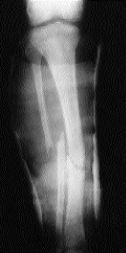

Figura 1. A: Fractura abierta Tipo IIIA tratada mediante fijador externo tipo Hoffmann. B: Radiografía anterposterior a los 8 meses de evolución.

C: Radiografía lateral.

La fijación externa, sigue teniendo un papel importante en el tratamiento primario de las fracturas abiertas de tibia,9,11,18,19,22,24 ya que permite una estabilidad adecuada de las fracturas y un buen acceso a la lesión de los tejidos blandos, sin compromiso de la movilidad de la rodilla o tobillo. Pero su empleo necesita de una técnica correcta para intentar evitar la complicaciones asociadas: aflojamiento de las fichas, infección en su trayecto, consolidación viciosa, retraso en la consolidación y pseudoartrosis.17 En nuestra serie el 59% de los pacientes presentaron algún tipo de complicación. El aflojamiento de las fichas suele ocurrir entre el tercer y sexto mes desde la aplicación del fijador,25 precisando o bien la revisión del fijador o bien completar el tratamiento con otro método coadyuvante, que varía desde la síntesis interna a la colocación de un yeso funcional. En nuestra serie la retirada del fijador se produjo con una media de 11 semanas, completándose el tratamiento con un yeso funcional tipo PTB. La infección en el trayecto de las fichas es una complicación relativamente frecuente que varía entre los 29% de Edwards y cols.11 y el 39% de Marsh y cols.,20 siendo del 9% de nuestra serie, que en casi todos los casos obligó a la retirada del fijador o a la revisión de esa ficha en concreto. En una fractura Tipo IIIB se des-arrolló una infección profunda del foco. Creemos que la menor incidencia de este tipo de complicaciones se deben a la menor gravedad de los tipos de fractura, así como al menor tiempo de persistencia de las fichas. El porcentaje de pseudoartrosis fue del 28%, relacionándose significativamente con el tiempo de mantenimiento del fijador y el tiempo de descarga, apareciendo sobre todo en las fracturas conminutas y en las de Grado II, aunque sin relación significativa (Fig. 1). El diagnóstico de pseudoartrosis se estableció aún cuando no habían transcurrido 9 meses desde la fractura, pero siendo evidente la ausencia de signos clínico y radiológicos de consolidación en los últimos meses. En ningún caso revisado se aportó injerto autólogo; creemos necesario, tal y como se encuentra descrito en la literatura,3,12,15 el aporte precoz de injerto autólogo para acortar el tiempo de consolidación y evitar la aparición de complicaciones. Todos los datos anteriores contribuyeron a que en la valoración global de resultados existió un 34,5% de malos resultados clínicos y un 31% de malos resultados radiográficos (Tabla 3). En los últimos tiempos la estabilización inmediata con enclavado endomedular (con o sin fresado) ha aumentado su popularidad para el tratamiento de las fracturas abiertas. Estas técnicas permiten un buen tratamiento de los tejidos blandos, con una buena estabilidad y alineación de las fracturas, junto a una movilidad precoz de rodilla y tobillo, así como una tasa de infecciones equiparables a las fracturas tratadas con fijación externa.6,10,28,29,32,33 Con las buenas perspectivas de este tratamiento no hay que olvidar sus posibles complicaciones: alteración de la vascularización endostal con el fresado, empleo de clavos sin fresar macizo de menor resistencia y diámetro, complicaciones en la introducción de un clavo sin guía, rotura del material y osteomielitis intramedular.